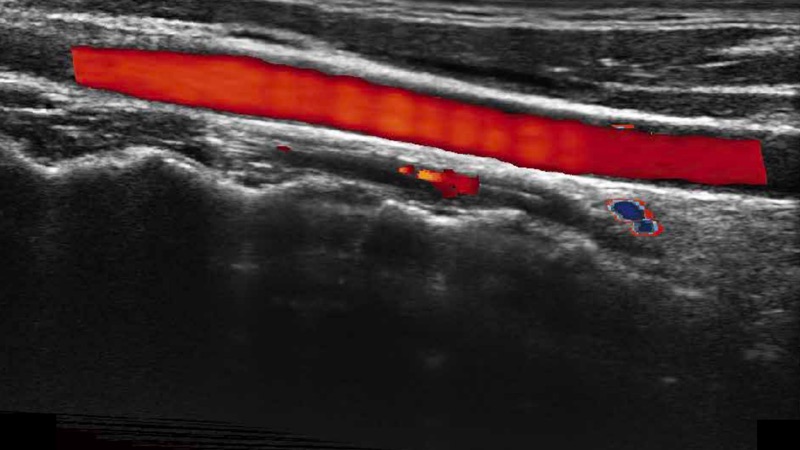

高分辨率血流成像技術(shù)提高了對低速血流信號的檢測能力。在提高空間分辨率的同時,也克服了血流外溢現(xiàn)象,為用戶提供更加真實的血流動力學(xué)信息。

通過色彩血流和實時寬景相結(jié)合,可觀察到完整的靜脈或動脈的血流,方便醫(yī)生檢查。實時掃查過程中,如有任何操作失誤也可以很容易地進(jìn)行回掃擦除,而不會中斷掃查。